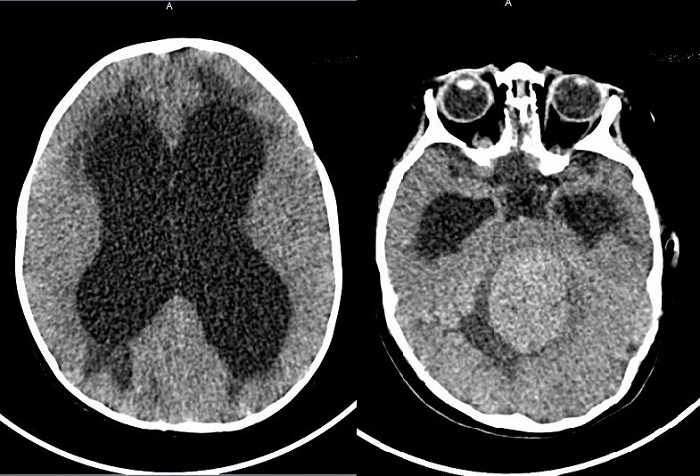

Ante la sospecha clínica de hipertensión intracraneal, se realizó una tomografía computarizada craneal urgente (Fig. 1) donde se observó una tumoración en la fosa posterior con hidrocefalia triventricular grave. Se trasladó a otro centro de tercer nivel, con diagnóstico radiológico final de meduloblastoma (tamaño 4,9 × 6,8 × 4,8 cm) con signos de diseminación leptomeníngea e hidrocefalia triventricular grave. Se realizó resección de la tumoración, con varios ingresos posteriores en Cuidados Intensivos Pediátricos por complicaciones y seguimiento actual por Oncohematología.

Figura 1. Tomografía computarizada craneal. Tumoración en fosa posterior con hidrocefalia triventricular grave